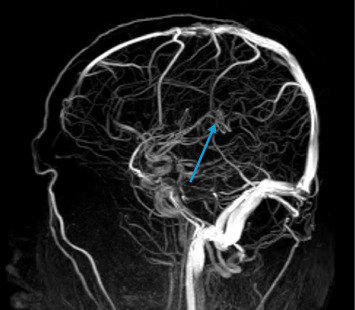

登革热由一种通过伊蚊传播的黄病毒引起,临床表现从轻微到严重不等。一些神经系统并发症,包括脑病和脑炎,已经被越来越多地认识到。在此,我们报告一例中心静脉血栓形成(CVT)作为登革热的感染后并发症。一名先前健康的38岁男性出现典型登革热症状,后来出现持续性头痛和视力障碍。神经学检查显示乳头水肿,影像学证实CVT累及上直窦。迅速开始抗凝治疗导致神经症状逐渐改善和血栓窦部分再通。我们的病例强调了在登革热感染中考虑血栓并发症的重要性,尽管出血表现占主导地位。了解登革热的病理生理学和适当的血栓事件管理对患者的良好预后至关重要。

Dengue fever, caused by a flavivirus transmitted through Aedes mosquitoes, presents a spectrum of clinical manifestations ranging from mild to severe. Several neurological complications, including encephalopathy and encephalitis, have been increasingly recognized. Here, we report a case of central venous thrombosis (CVT) as a postinfectious complication of dengue fever. A 38-year-old previously healthy male presented with classic dengue symptoms and later developed persistent headaches and visual disturbances. Neurological examination revealed papilledema, and imaging confirmed CVT involving the superior straight sinus. Prompt initiation of anticoagulant therapy led to gradual improvement in neurological symptoms and partial recanalization of the thrombosed sinus. Our case underscores the importance of considering thrombotic complications in dengue infections, despite the predominance of hemorrhagic manifestations. Understanding pathophysiology and appropriate management of thrombotic events in dengue fever is crucial for favorable patient outcomes.